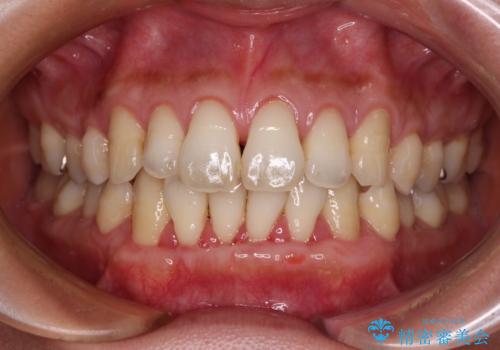

- 年々歯肉退縮が進行することを気にして来院された患者様です。

歯肉が菲薄であることが経年的な進行の原因であることが推察されたため、上顎からの結合組織移植術(CTG)により、歯根の被覆を行うとともに、歯肉の厚みを増すことで将来の退縮リスクを抑制することとしました。